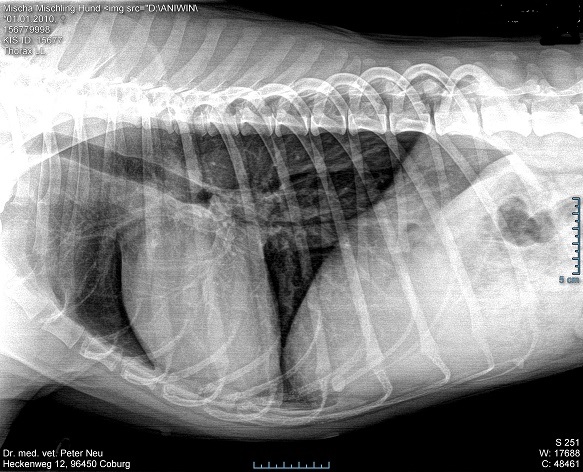

Die Aufnahme zeigt verdickte und entzündete Pulmonalarterien, in einem mittleren Umfang. Mischa bekommt nund eine Medikament aus der Auslandsapotheke “Melarsomin” Kosten im Einkauf schon über 350 Euro. Diese Behandlung sollte gut vetragen werden, weil die Veränderungen am Herzen noch nicht ganz so weit fortgechritten sind